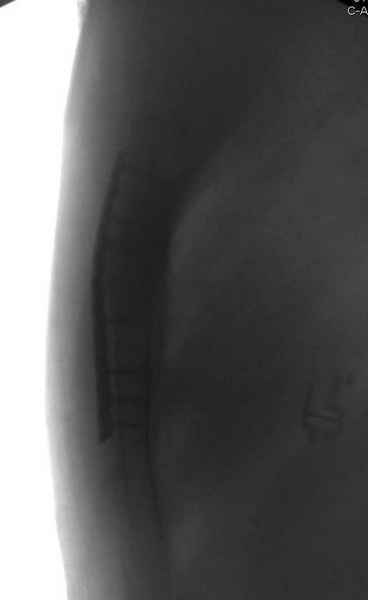

Юра, интересно, насколько такой остеосинтез контролирует степень репозиции, а то у меня имеются снимки девочки 11 лет, направленной ко мне на консультацию из одной из республик бывшего союза.

После торакальной операции, по-видимому, сильно натянули проволоку, и в результате получился захлест отломков в друг друга.

С такими продольными несращениями мне не приходилось иметь дело, поэтому направил в один из центральных институтов детской ортопедии России.

А простые посттравматические ложные суставы грудины приходилось оперировать с ограничителем сверла и с фиксацией 2.4 мм пластинами с угловой стабильностью.